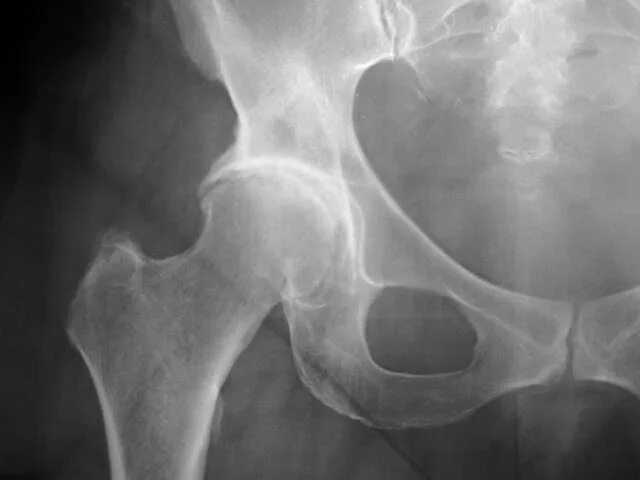

Остеоартроз тазобедренных суставов 1 2